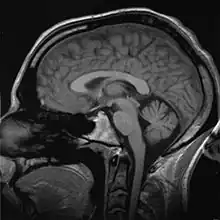

Ce fut d'abord le scanner qui permit de visualiser, pour la première fois le cerveau et les zones corticales avec une précision remarquable, puis la résonance magnétique nucléaire (IRM) a considérablement modifié, à son tour, l'étude iconographique des structures corticales.

En 1938, le principe de résonance magnétique nucléaire est découvert par Isidor Isaac Rabi. Cette découverte aboutira, en 1973, à la mise au point de ce qui allait devenir l'imagerie par résonance magnétique ou IRM, simultanément par Paul Lauterbur et Peter Mansfield qui reçurent conjointement un prix Nobel (Prix Nobel de physiologie ou médecine) en 2003.